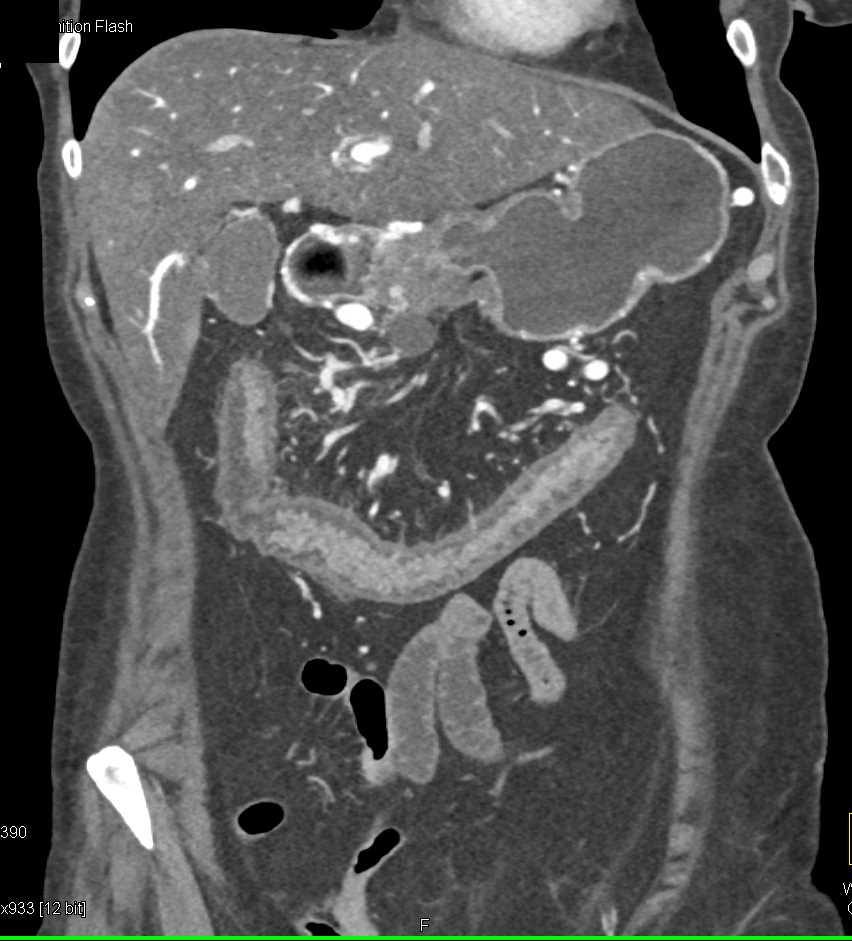

Pancreatic Cancer with Vessel Encasement and Involvement of the Transverse Colon seen